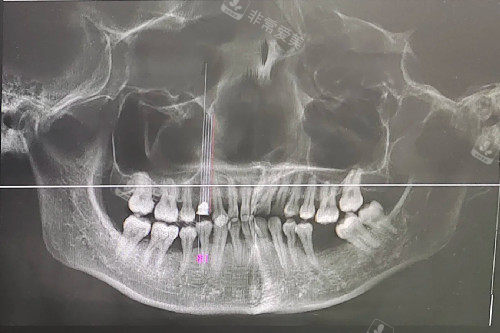

牙周炎症照片